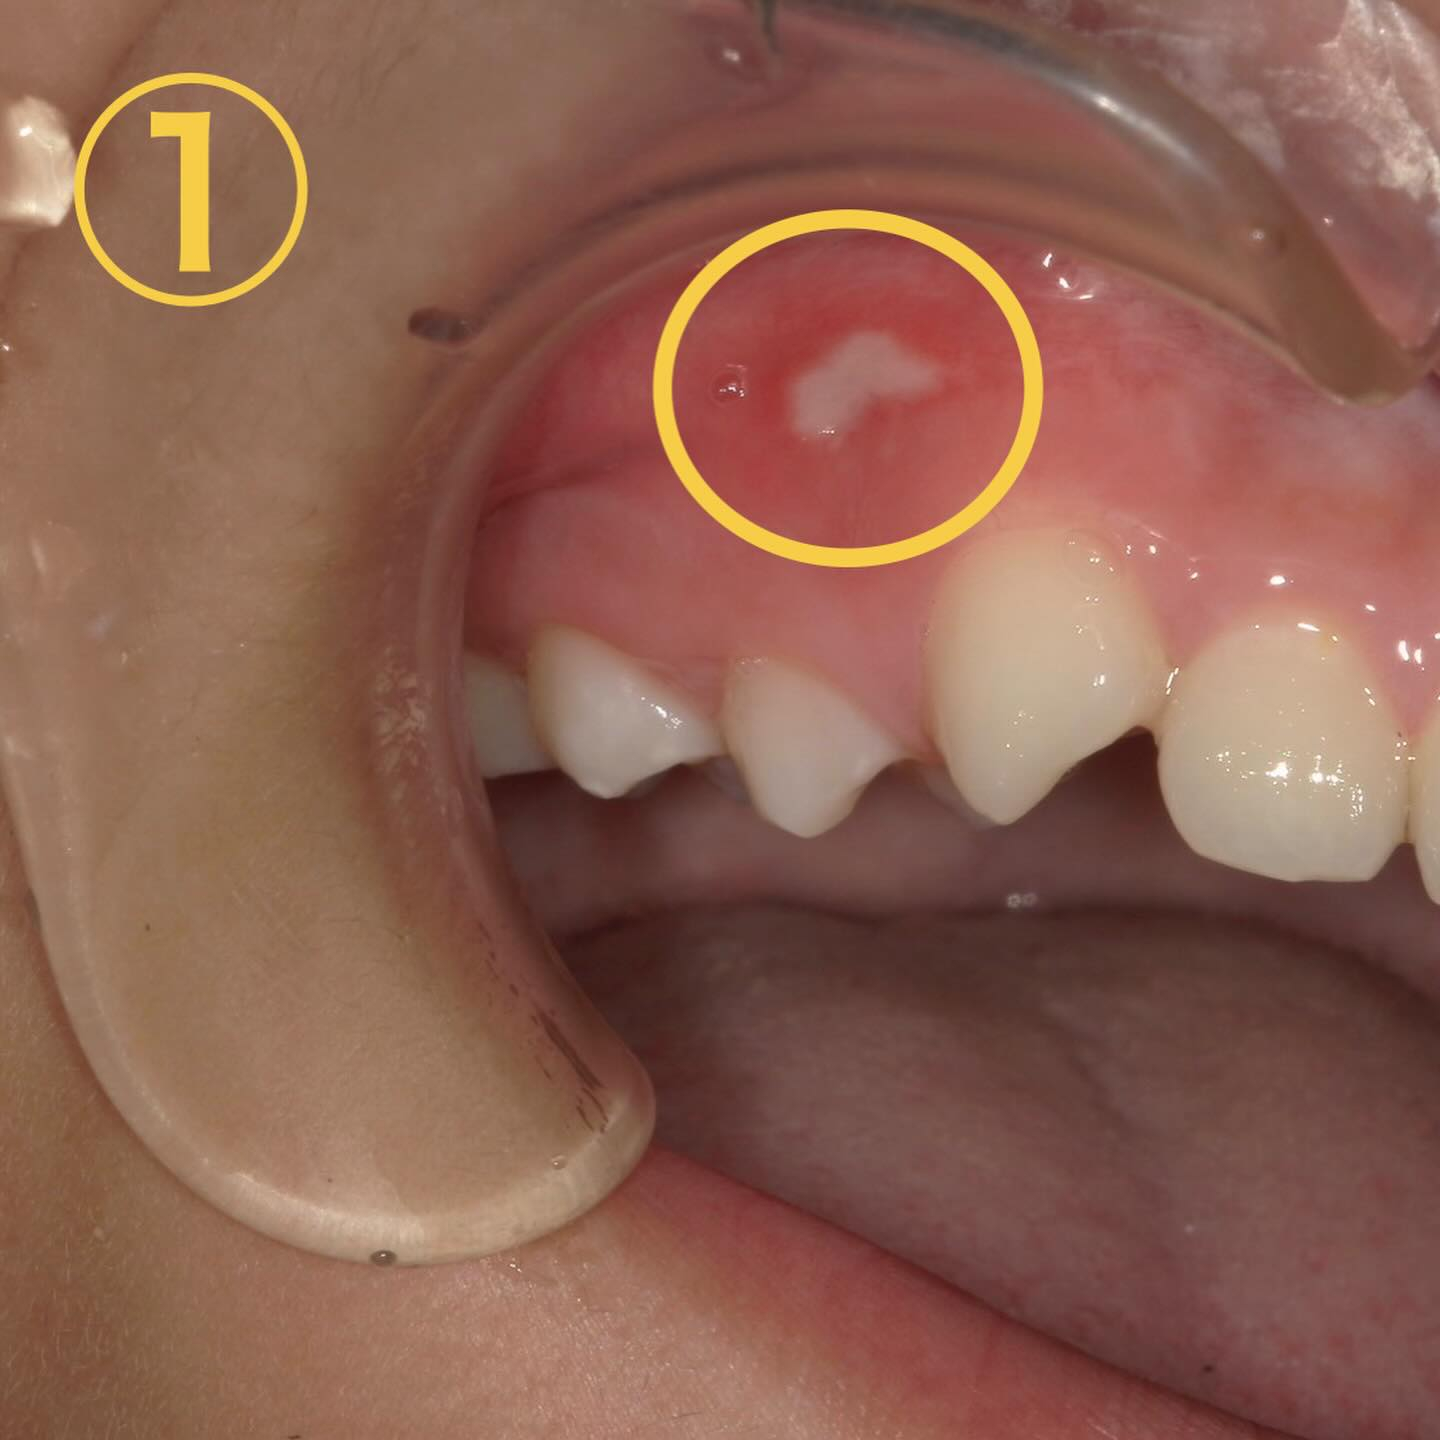

まず、画像①、②は典型的な口内炎です🧐

お二人とも歯磨き中に歯ブラシが滑って歯茎に当たったと仰ってました😱

特徴→・痛みがある・物が当たった等、原因となる心当たりがある・数日すると治って繰り返さない

💊治療法→塗り薬もあるのですが唾液で流れやすい為結局は経過観察がメインになります🥲